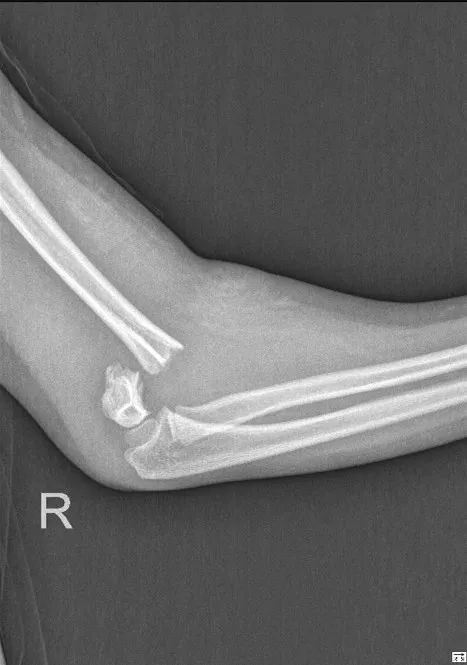

紧急送往我科检查,发现肱骨髁上骨折。

X光片正位片侧位片显示远端移位。